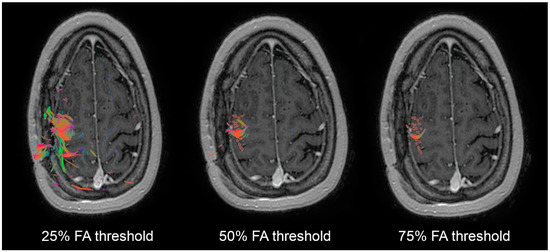

| Tractography at 25% FA | Deficit | No Deficit | Tractography at 50% FA | Deficit | No Deficit | Tractography at 75% FA | Deficit | No Deficit |

|---|---|---|---|---|---|---|---|---|

| Resection | 6 | 15 | Resection | 6 | 6 | Resection | 6 | 1 |

| Preservation | 1 | 29 | Preservation | 1 | 29 | Preservation | 1 | 34 |

| Yes | 12 | 6 (50%) | 29 | 2.93–287.02 | 0.004 |

| No | 29 | 1 (3.4%) | |||

| Resection of 75% FAT TMS WMTs | |||||

| Yes | 7 | 6 (86%) | 204 | 11.17– 3724.26 | <0.0001 |